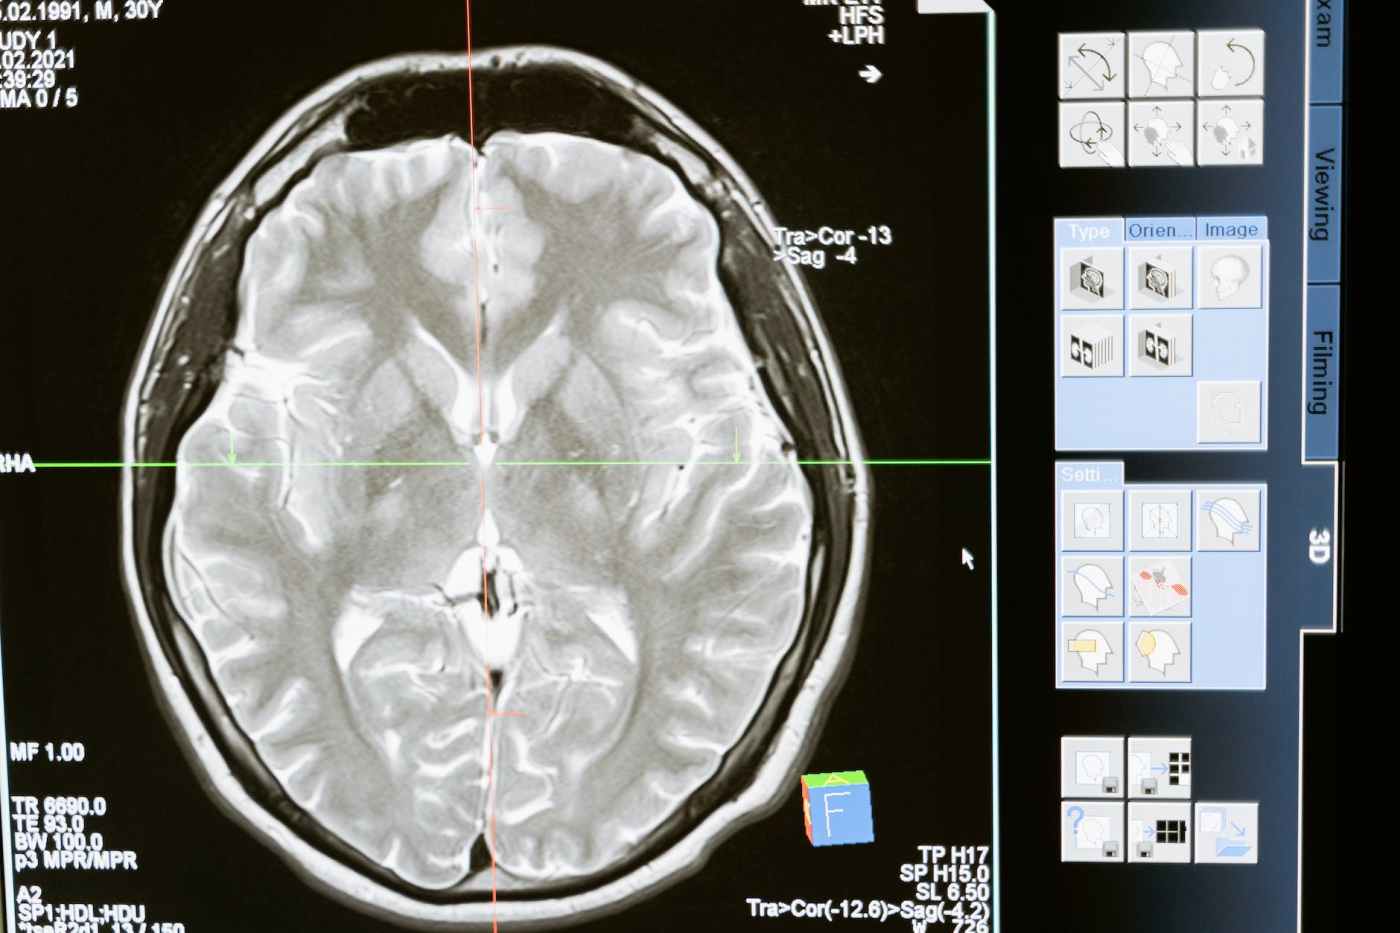

It actually costs a lot to pay a little attention. Source: Your Brain Is Bad at Doing Everything Everywhere All at Once